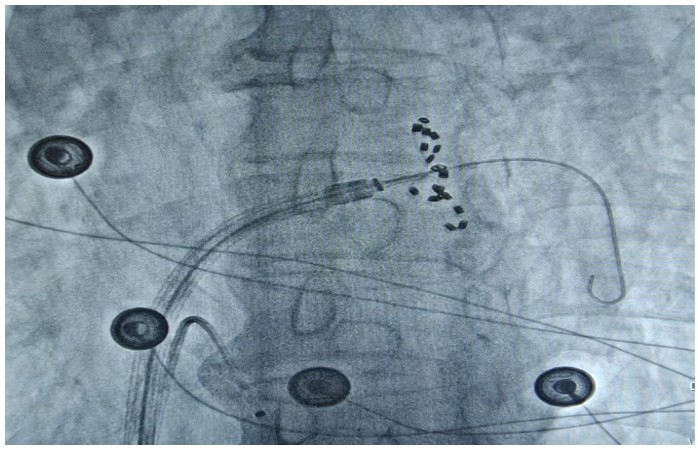

通訊員何紅丹報(bào)道:2025年1月17日,衡陽(yáng)市中心醫(yī)院心血管內(nèi)科趙慶禧主任醫(yī)師團(tuán)隊(duì)與心血管內(nèi)科電生理團(tuán)隊(duì)協(xié)作,在全麻下成功為一名72歲的男性患者實(shí)施了陣發(fā)性房顫FARAPULSE脈沖電場(chǎng)消融手術(shù)。此次手術(shù)為目前全球最先進(jìn)的PFA消融導(dǎo)管上市后全國(guó)首批臨床應(yīng)用,在湘南地區(qū)首次開(kāi)展,能更精準(zhǔn)地作用于目標(biāo)區(qū)域,減少對(duì)周?chē)M織的損傷,極大程度降低并發(fā)癥的發(fā)生,具有更高的安全性。

趙慶禧介紹,房顫是常見(jiàn)于老年人的心臟問(wèn)題,通俗的講就是心臟“亂跳”。發(fā)生房顫時(shí)患者心慌心悸難忍,極易誘發(fā)腦卒中等惡性后果,嚴(yán)重危害生命健康。目前,房顫的治療方法包括藥物治療和傳統(tǒng)導(dǎo)管消融。相較于藥物治療和傳統(tǒng)導(dǎo)管消融,脈沖電場(chǎng)消融可選擇性的損傷心肌,而保留血管、神經(jīng)及心臟周?chē)M織。更快的消融脈沖電場(chǎng)消融(PFA)技術(shù)是最新的消融技術(shù),它能通過(guò)高壓電脈沖,實(shí)現(xiàn)消融點(diǎn)細(xì)胞凋亡的目的,達(dá)到抑制紊亂心律發(fā)生的作用。與傳統(tǒng)消融技術(shù)相比,脈沖電場(chǎng)消融具有更高的組織選擇性、更快的消融速度以及更低的貼靠要求,成為臨床迫切需要的突破性創(chuàng)新治療方法,為患者帶來(lái)了新的選擇和新的希望。